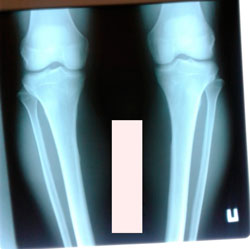

Дата операции - 08.10.2020

Дата снятия аппаратов - 16.01.2021